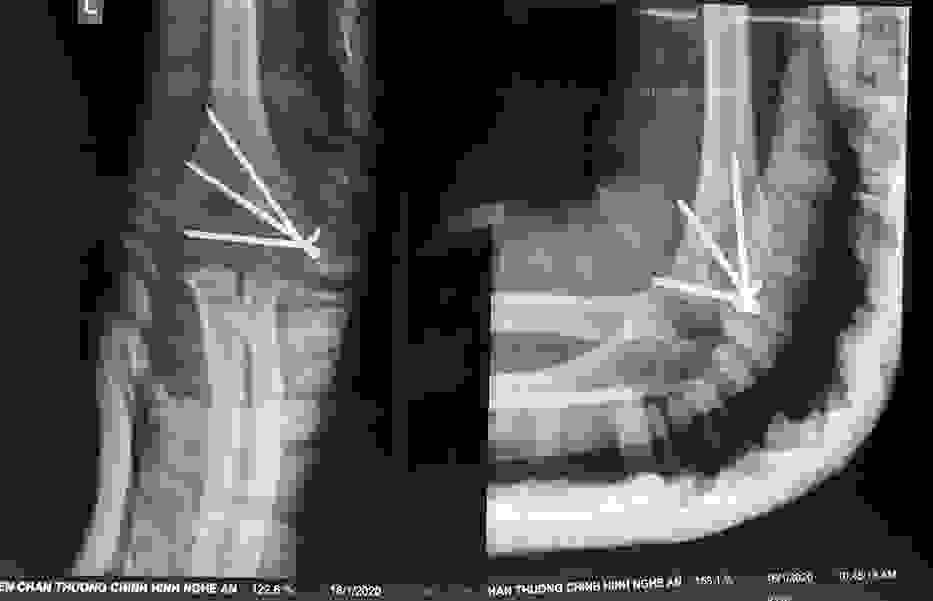

Chấn thương nhi: Gãy trên hai lồi cầu xương cánh tay

Gãy trên lồi cầu xương cánh tay là loại gãy vùng khuỷu phổ biến ở trẻ em trong lứa tuổi từ 5-12 (đặc biệt ở trẻ 8 tuổi).

Điều trị gãy lồi cầu ngoài xương cánh tay ở trẻ em

Đã xem: 5798